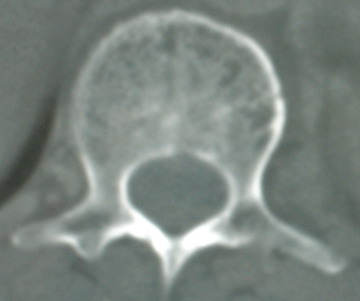

以下是引用jinguoji在2008-6-3 20:20:00的发言:[br]双上肺弥漫性小结节影,纵隔窗内钙化淋巴结影,考虑血播性tb可能性较大,不除外肺ca可能。腰椎考虑退变。